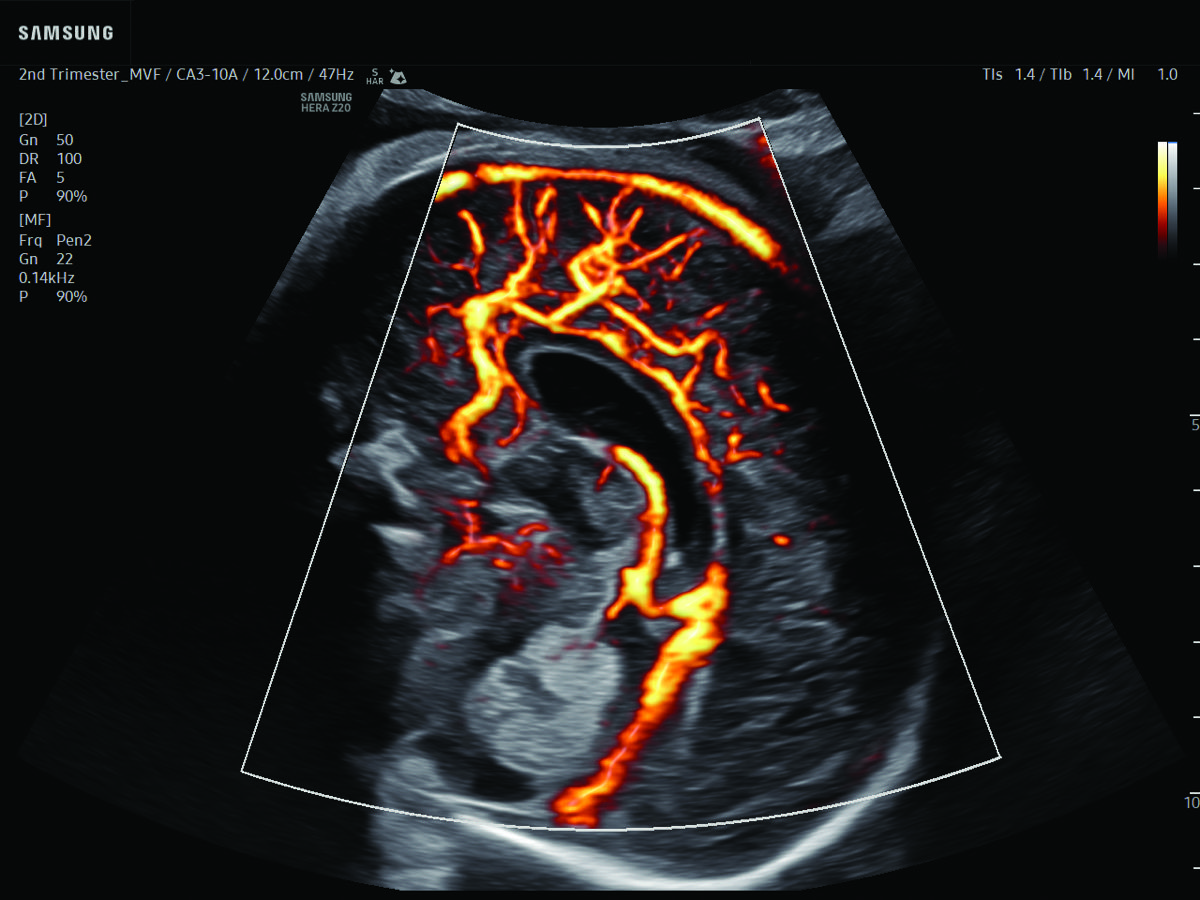

Comprehensive, advanced and expert MFM care for high-risk pregnancies

- Fetal anomalies